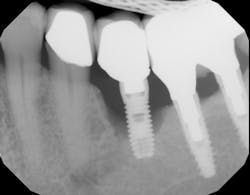

Recent studies suggest a role of SSRI intake and reduced bone mineral density, with an increase in bone fracture.4 The effect of SSRI use on implant success rates is not clear, but one study evaluated 94 implants placed over five years and saw a double in implant failure rates when comparing patients taking SSRIs and those not taking the medication.5 Another more recent study evaluated 2,055 implants placed over a two-year period. This study suggested a threefold increase in the number of failures in patients taking SSRIs compared to those who did not take the medication.6 When unexplained bone loss occurs around an implant and the patient has been on a long-standing SSRI medication, consideration should be given to this possible etiology (figure 1).

The effect PPIs have on implants is not clear, but one study looked at 3,560 implants placed in 1,000 patients over a 35-year period. Results found a 12% failure rate in PPI users versus nonusers.8 Another study evaluated 1,773 implants placed in 800 patients and found the failure rate doubled when comparing PPI users and nonusers.9 When unexplained bone loss occurs around an implant and the patient has been on long-standing PPI medication, consideration should be given to this possible etiology (figure 2).